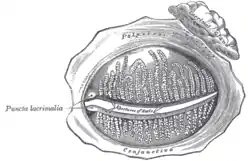

The tarsal glands, etc., seen from the inner surface of the eyelids. (Puncta lacrimalia visible at center left.) | |

The lacrimal punctum (pl.: puncta) or lacrimal point, is a minute opening on the summits of the lacrimal papillae, seen on the margins of the eyelids at the lateral extremity of the lacrimal lake. There are two lacrimal puncta in the medial (inside) portion of each eyelid. Normally, the puncta dip into the lacrimal lake.

Together, they function to collect tears produced by the lacrimal glands. The fluid is conveyed through the lacrimal canaliculi to the lacrimal sac, and thence via the nasolacrimal duct to the inferior nasal meatus of the nasal passage.